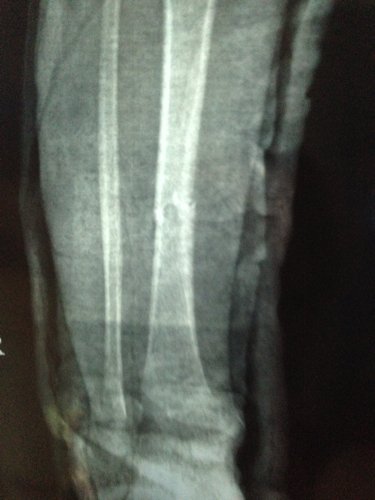

男孩三周岁 5-9 被电动车撞,右小腿胫骨骨折,正位对线良好,侧位错位三分之一。现差不多六周,前两天腿甩痛了就近急诊拍片,医生说骨头在长的,一周后把石膏拆掉吧,否则肌肉萎缩影响走路的,请各位医生指点一下,错位情况下,石膏拆了会影响恢复吗?因为两段骨头没合上阿,我上传一张之前的片子,请大家帮忙看一下。